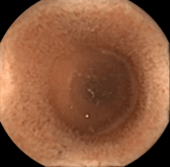

Capsule endoscopy is a way to record images of the digestive tract for use in medicine. The capsule is the size and shape of a pill and contains a tiny camera. After a patient swallows the capsule, it takes pictures of the inside of the gastrointestinal tract. The primary use of capsule endoscopy is to examine areas of the small intestine that cannot be seen by other types of endoscopy such as colonoscopy or esophagogastroduodenoscopy (EGD).